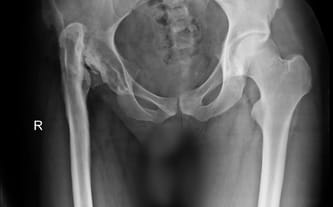

Cel zbiórki: Dwuetapowa operacja rekonstrukcji stawu biodrowego oraz wydłużenia nogi

Stan po zakażeniu gronkowcem złocistym, czterech operacjach stawu biodrowego oraz dwóch etapach wydłużania kości udowej